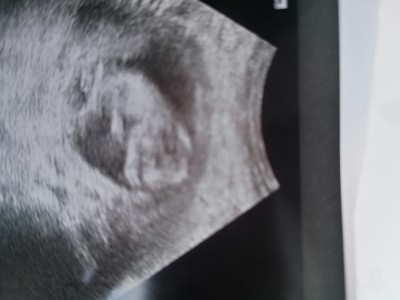

12 haftalık hamileyim ikili tarama için gittik ama yan pozisyonda olduğu için tahminde bulunamadı doktor bi tahmini olan var mı acaba